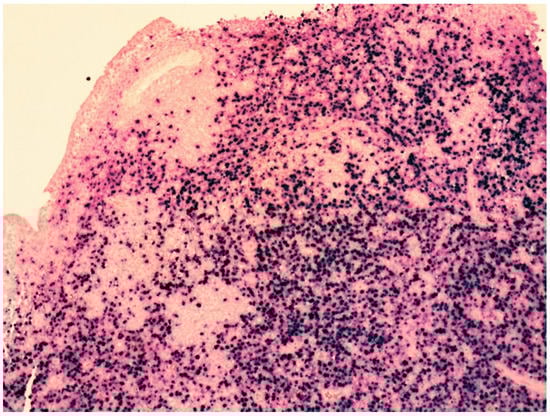

| Histology | Large-sized cells within medium- to small-sized vessels | Polymorphic cells, clear cytoplasm; inflammatory background, necrosis. Angioinvasive and angiodestructive pattern. | Variable in size from normal granular lymphocytes to large, atypical cells | High-grade morphology (either polymorphic or monomorphic) |